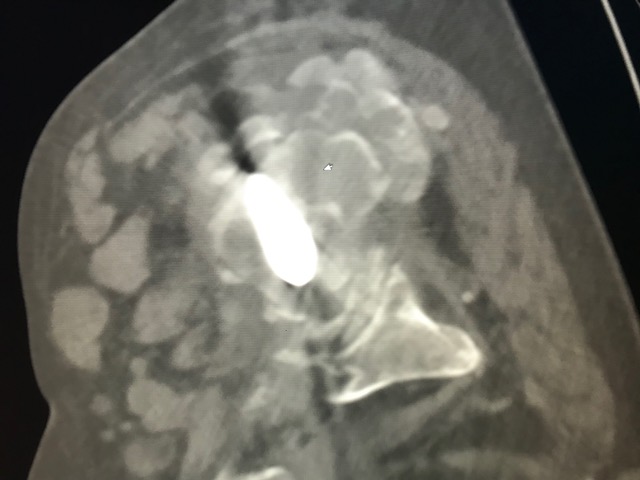

Figure 3 for case Tumoral calcinosis ( RID5202 )

Figure 3